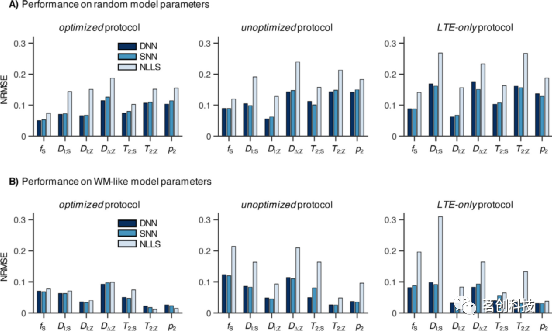

采集协议对网络精度和灵敏度的影响

本节将重点讨论采集协议设计与网络性能之间的关系。图3显示,基于ANN的拟合可以部分但不能完全消除未优化和LTE-only协议中已知的拟合简并:基于优化协议的ANN比基于其他两种协议的ANN提供了更低的估计误差(NRMSE)。比较这两个协议可以发现,未优化协议对DI;S和T2;Z的估计相对更准确,而LTE-only协议对fS、DI;Z、DΔ;Z、T2;S和p2的估计更准确。图3还表明,与传统的NLLS方法相比,SNN和DNN的性能受次优采集协议的影响较小(图3)。对于NLLS方法,使用未优化或LTE-only协议会导致估计误差显著增加,而对于DNN或SNN方法,仅观察到NRMSE略有增加。这表明ANNs可以在一定程度上缓解由与微观结构模型相关的协议不充分而导致的参数估计困难。

图3.优化的采集协议使得基于ANN和NLLS的参数估计误差更小。